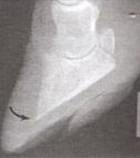

Taban Ucu Ülseri

Klinik Bulgular

• Tırnak ucunda

• basit tırnak lezyonu

• enfekte osteoliz

• Ayrılma

• uzama

• Hafif veya şiddetli toplalık

• Ökçelere basma

• İleri duruş pozisyonu

• İleri durumda koryum açığa çıkar